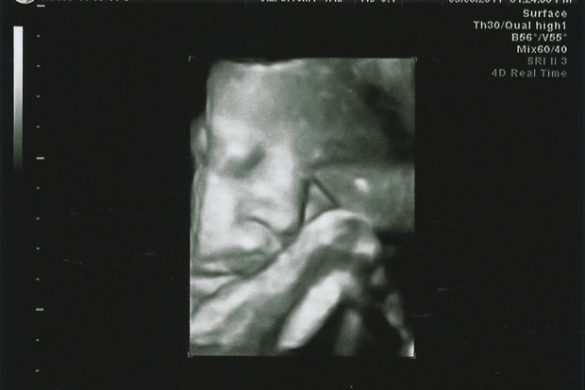

We headed into the doctor’s office Friday ready to see how our little guy was doing. In the ultrasound, everything looked great. Lungs were there…heart was beating away…he even estimated out to 6 lbs 11 oz which is really good for being over 3 weeks early. The doctors decided he was ready to go.